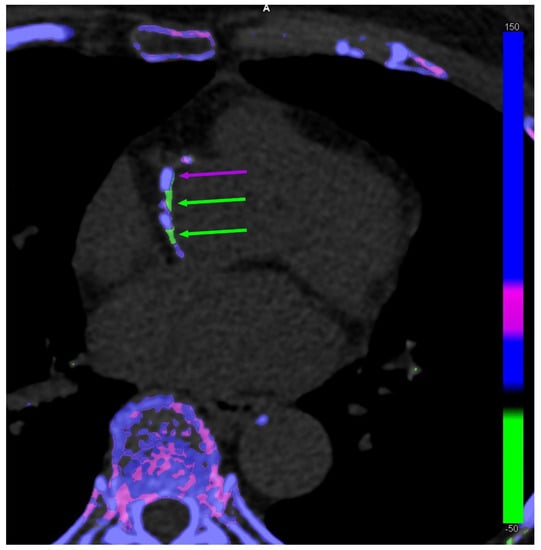

The discussion on the potential existence of arterial MSU crystal deposition was renewed by the publication of DECT scans of coronary arteries and the aorta from patients with gout and controls by Klauser et al. [13] (Figure 1). The study included 59 patients with gout who were compared to 47 controls. Using the post-processing software in ‘gout mode’, vascular plaques were coded by the machine as containing MSU crystals in the aorta more commonly among patients with gout (n = 51 [86.4%]) compared with controls (n = 7 [14.9%]) (χ2 = 17.68, p < 0.001), as well as in coronary arteries (n = 19 [32.2%] vs. n = 2 [4.3%]) (χ2 = 8.97, p = 0.003), respectively. Another important finding was that the coronary calcium scores (i.e., the extent of calcified plaques) was significantly higher in patients with gout than in controls, suggesting that there may be a relationship between calcified plaques and MSU-coded plaques. The same team performed other studies with similar methodologies, including analyses using crystal-containing phantoms providing the same results, which were also found in a small study by another team using the same methodology [21,22]. Methodological issues were raised in response to the publication of the first study, but at least the question was opened [23].

Figure 1.

Dual-energy computed tomography of co-existing monosodium urate (MSU) crystal-coded (green arrows) and calcium-coded (purple arrows) coronary plaques in a 63-year-old female patient without gout.